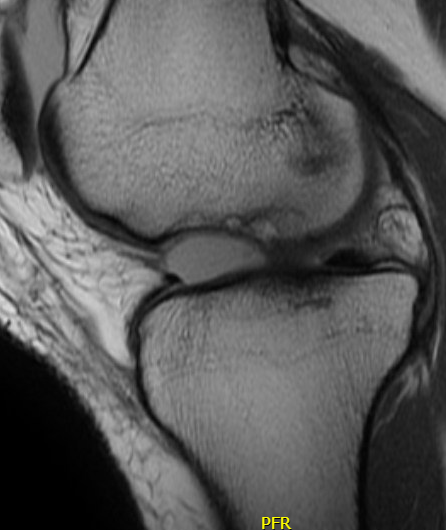

Chondral defect

Osteochondral defect